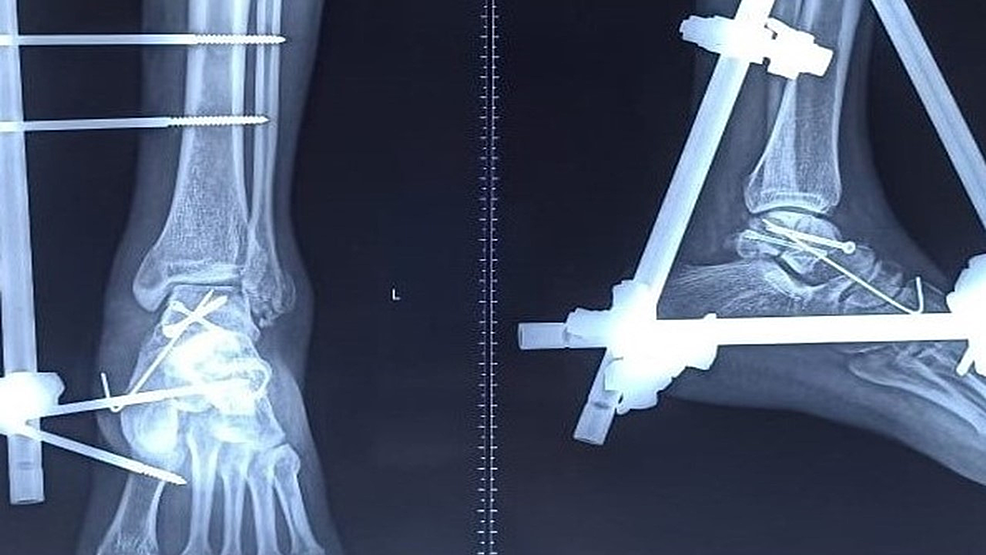

If you experience a fractured (broken) talus, you might. Talar fracture surgery repairs a break in the talus, a bone that makes up part of the ankle joint and the subtalar joint. The talus meets your tibia (shin bone) and fibula (calf bone) to form your ankle joint. Treatment may be as simple as a cast or a splint, or it may involve surgery. Surgery to treat an open talus fracture often involves much more than lining up the broken pieces of bone. But if the broken bone is in a good position and is stable, you might be treated with just a splint or cast. Either way, you'll want to keep your weight off the injured ankle at first. Be gentle with yourself during recovery and give your bones time to heal. The healing process can take a while. Pins or screws may be needed, as well as treatment of the damaged.

Talus Bone Surgery Be gentle with yourself during recovery and give your bones time to heal. Gradually you'll be able to add more and more weight as the bone heals. Surgery to treat an open talus fracture often involves much more than lining up the broken pieces of bone. The surgery realigns the bone. But if the broken bone is in a good position and is stable, you might be treated with just a splint or cast. Either way, you'll want to keep your weight off the injured ankle at first. Treatment may be as simple as a cast or a splint, or it may involve surgery. Most of the time, you need surgery for a talus fracture. The talus meets your tibia (shin bone) and fibula (calf bone) to form your ankle joint. Be gentle with yourself during recovery and give your bones time to heal. The healing process can take a while. Pins or screws may be needed, as well as treatment of the damaged. If you experience a fractured (broken) talus, you might. If the bones are far out of. Talar fracture surgery repairs a break in the talus, a bone that makes up part of the ankle joint and the subtalar joint.

Figure 8 from Talar neck and body fractures. Semantic Scholar Talus Bone Surgery If the bones are far out of. Pins or screws may be needed, as well as treatment of the damaged. The talus meets your tibia (shin bone) and fibula (calf bone) to form your ankle joint. Most of the time, you need surgery for a talus fracture. Surgery to treat an open talus fracture often involves much more than lining. Talus Bone Surgery.